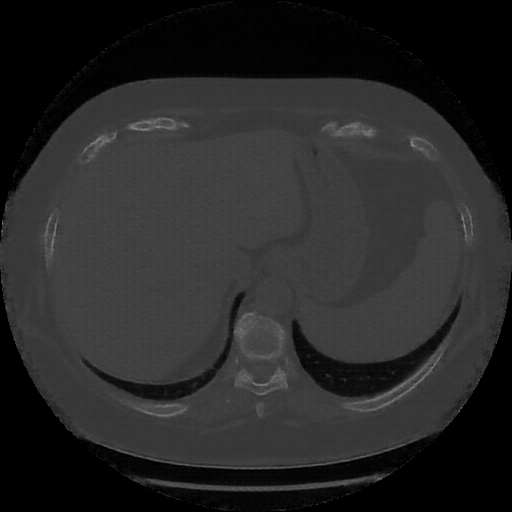

Original NATIVE CT scan (input)

Mediastinum window (WL 40, WW 400 β†’ Low βˆ’160, High +240)